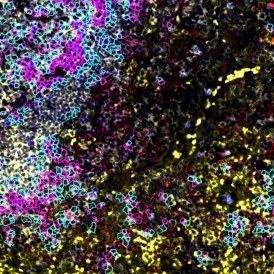

How to Carry Out Complex Characterization of the Tissue Microenvironment

Characterizing the tissue microenvironment reveals how cells and structures interact in health and disease. This blog highlights its role in cancer research and how TissueGnostics solutions enable advanced imaging and quantitative analysis.